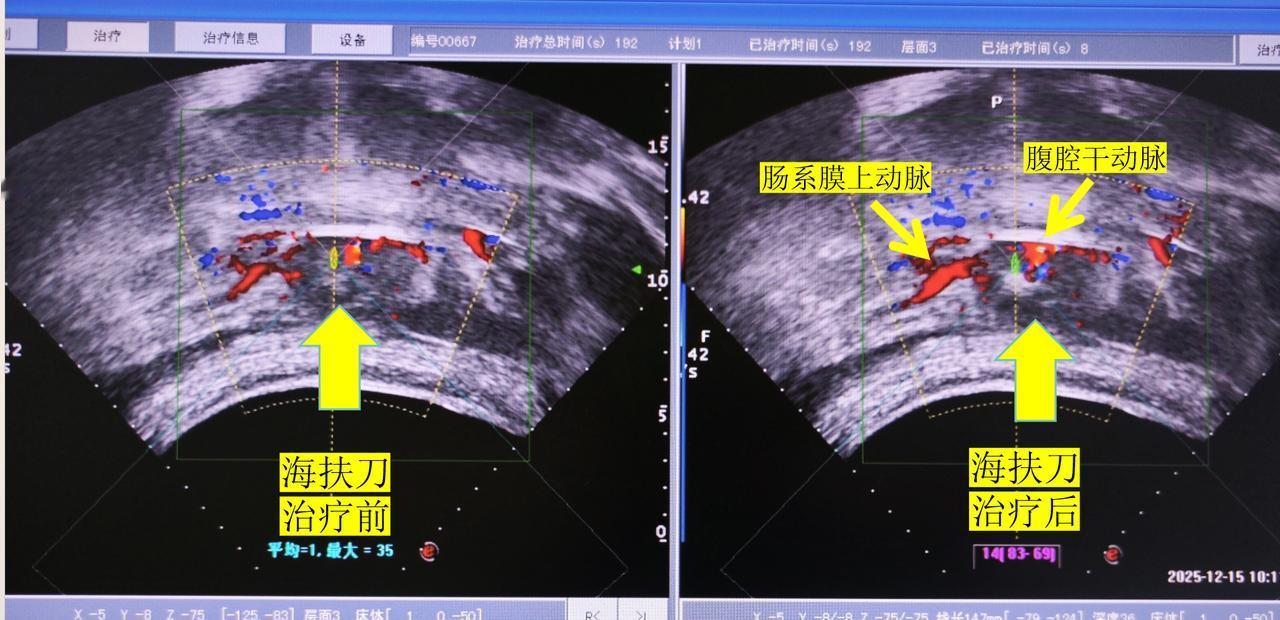

陈谦海扶刀治疗侵犯血管晚期胰腺癌病例11433号 这是我们今天海扶刀治疗的一名晚期胰腺癌患者,病人59岁,病人初期表现为腰痛和腹部疼痛,至当地医院检查,按照胃病口服对症治疗后,疼痛没有得到有效控制,后到梅河口中心医院进一步检查,CT确诊为胰腺癌。 术前CT显示肿瘤已经将腹腔干动脉和肠系膜上动脉完全包饶侵犯,病灶前方是胃腔,胃扩张比较厉害,可能是肿瘤压迫肠道导致有一定的梗阻,右侧紧邻十二指肠,后方就是腹主动脉。 对于这种情况,首先患者没有手术机会,肿瘤已经将血管侵犯无法安全剥离; 化疗是可以选择的方法,但是胰腺癌对化疗一般不明,少数患者也可以化疗后肿瘤缩小从而达到手术的要求; 放疗也是胰腺癌常常选择的方式,不过病灶前方是胃,由于可能导致放射性胃肠炎,所以相对来说不作为首选; 部分医院可能会推荐做临床试验,如果没有更好的治疗方法或者各种治疗方法失败的情况下,也是可以选择的。 我们的治疗方案是海扶刀治疗加上口服化疗药,今天首先是将肿瘤大部分杀灭,降低肿瘤负荷后再靠药物将残留的肿瘤细胞杀灭,是有可能达到长期带瘤生存的效果,并且海扶刀可以同时破坏腹腔神经丛,缓解疼痛,提高生活质量;一般术后第二天患者就可以恢复正常生活。 术中实时超声也可以显示,肿瘤虽然包饶血管,但是我们海扶治疗可以看到肿瘤明显的回声改变,这是肿瘤发生凝固性坏死的超声表现。 所以对于晚期胰腺癌侵犯血管的患者,海扶刀治疗是非常安全有效的,还是非常具有优势。 胰腺癌治疗 海扶刀